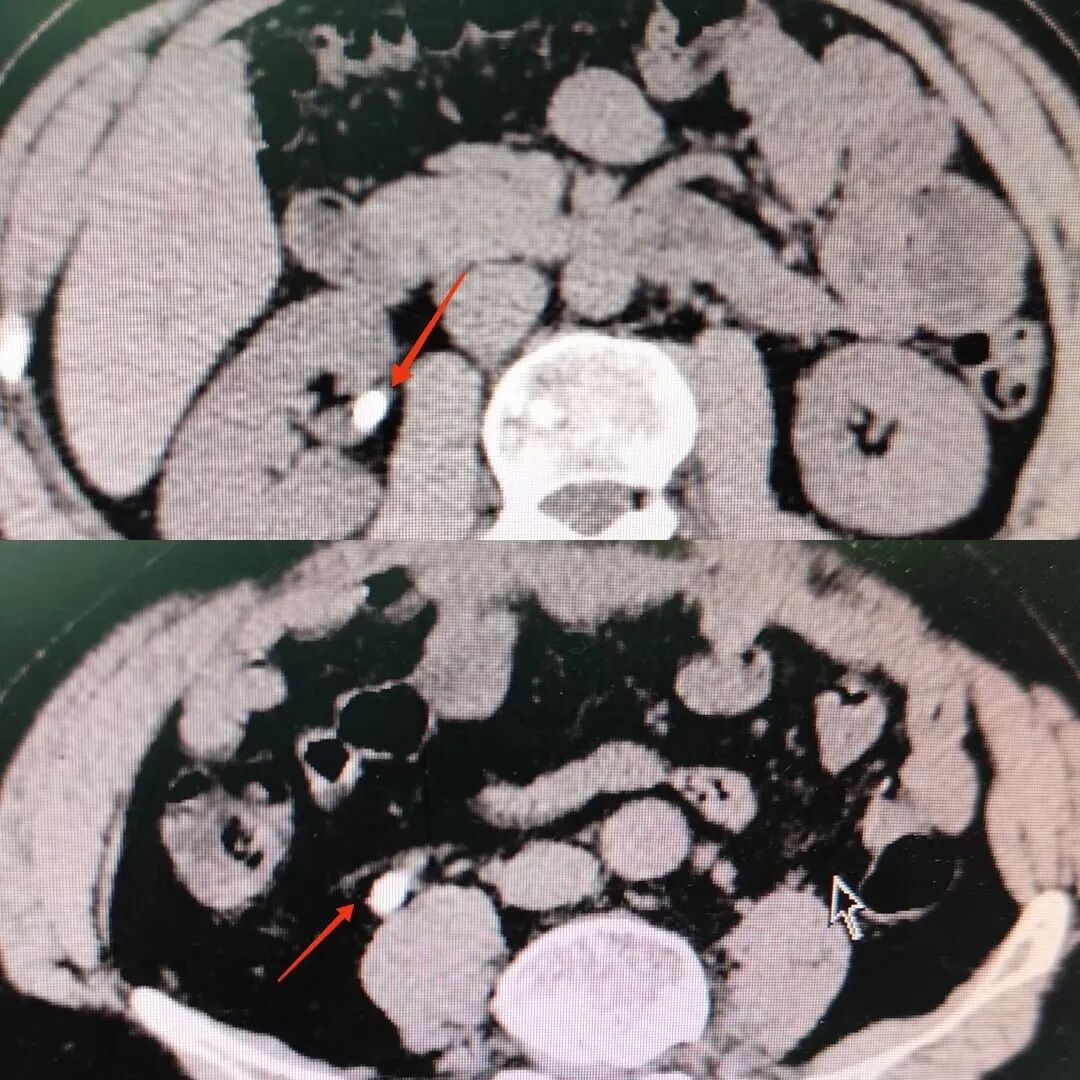

夏季炎热,气温升高,泌尿系结石的发病人数明显增多,近期泌尿外科收治的结石病人随之增加。小陈就是其中的一位,半夜突然左腰腹部疼痛难忍,他以为是普通的腹痛,想喝点热水,躺躺就好。可是半个小时过去了,疼痛更加剧烈,还伴有呕吐,血尿。受不了了,他马上打车到医院。经过急诊医师的初步检查,判断他可能是泌尿系结石梗阻了。经过CT检查,确诊左输尿管结石,收住泌尿外科进一步治疗。

一般可通过B超、腹部平片、CT、尿路造影、磁共振等检查发现。